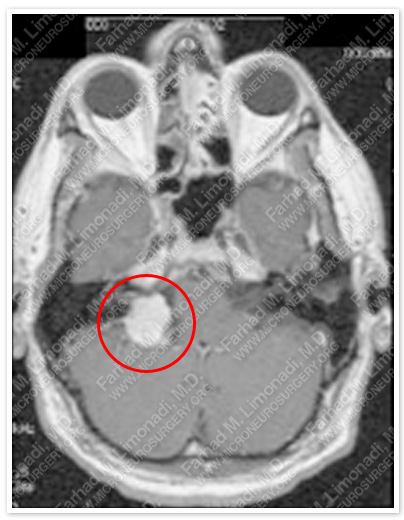

Imaging

MRI scan of patient’s brain shows a recurrent large right acoustic neuroma